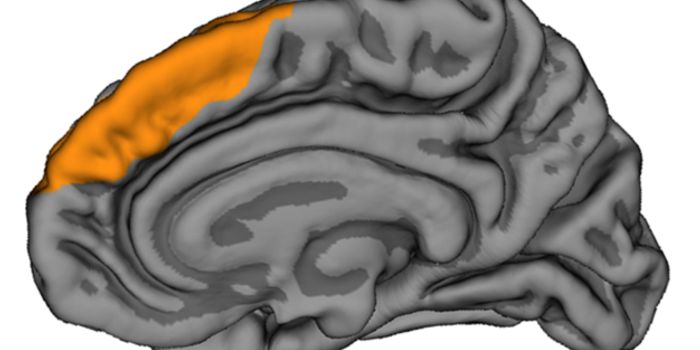

NOV 19, 2015Clinical & Molecular DXCould a shorter brain fold be diagnostic of hallucinations associated with schizophrenia? After analyzing the MRI scans ...